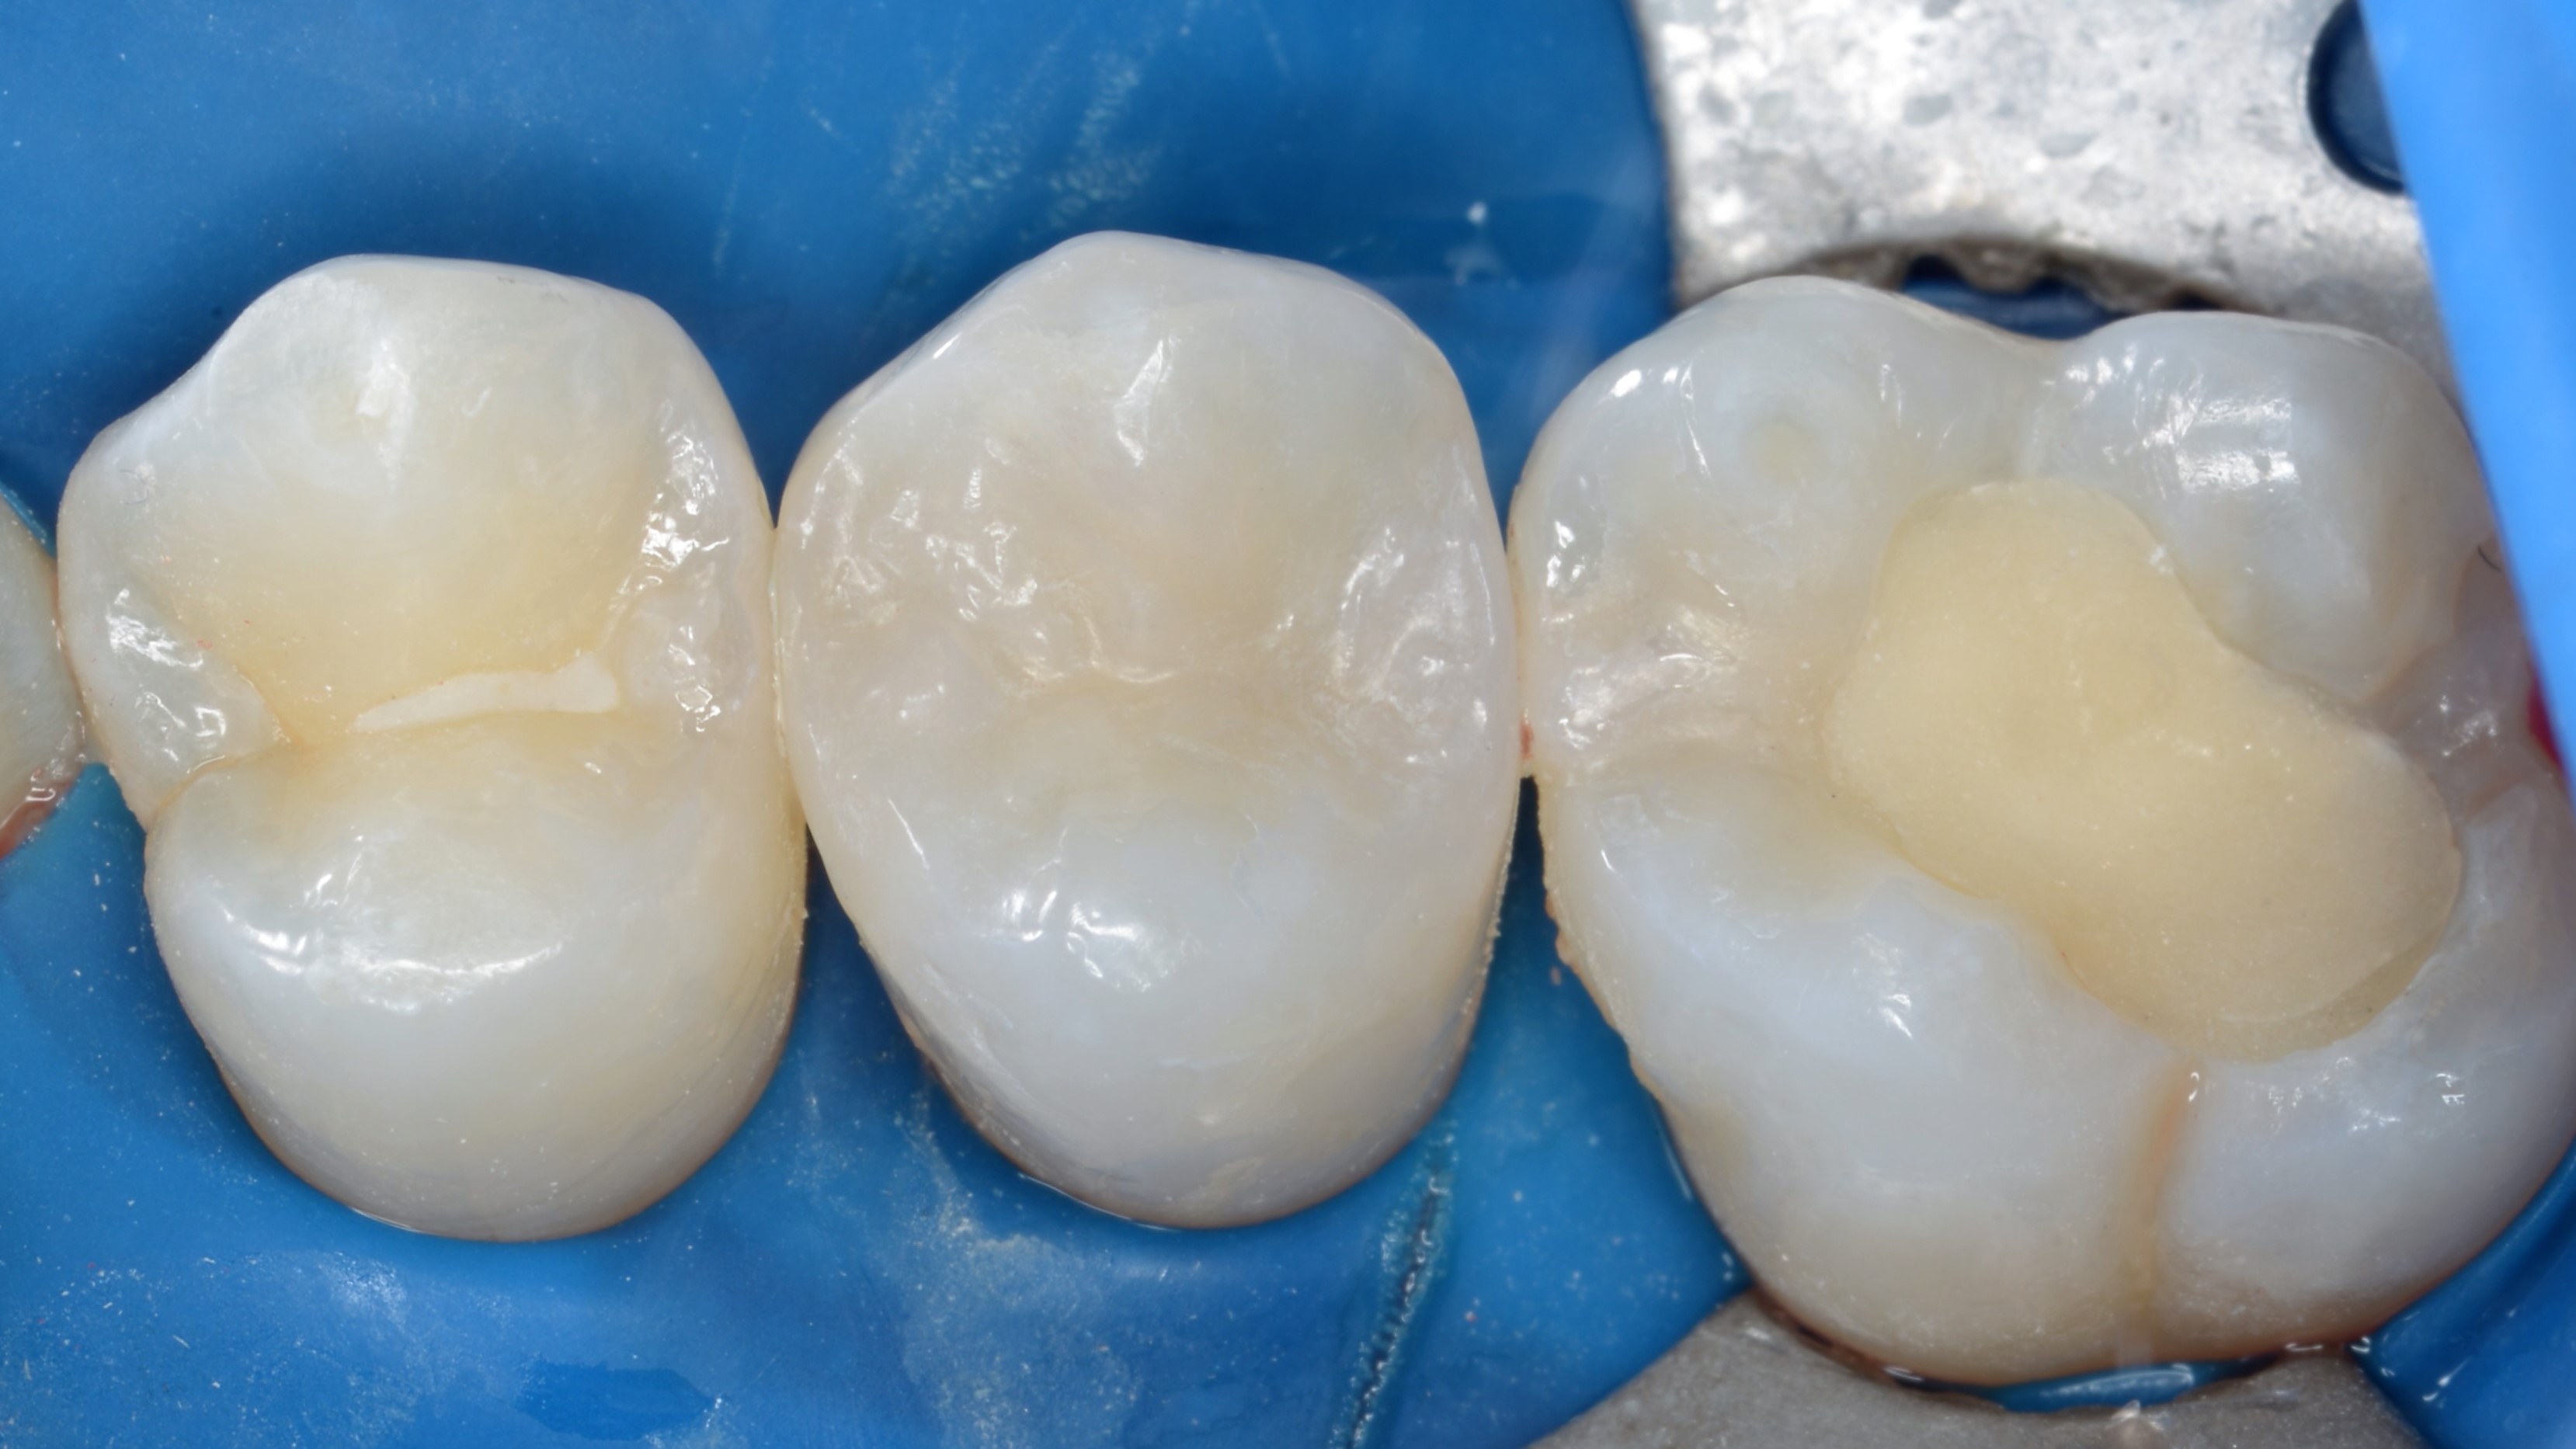

Z powodu pandemii COVID-19 kontynuacja leczenia odbyła się po 6 miesiącach. W wywiadzie pacjent nie zgłaszał dolegliwości bólowych zęba 15. Na drugiej wizycie ponownie sprawdzono żywotność zęba – reakcja na chlorek etylu była prawidłowa, ząb nie reagował bólem na opukiwanie. W znieczuleniu nasiękowym, w osłonie koferdamu i powiększeniu mikroskopu usunięto pozostałości wypełnienia tymczasowego oraz opracowano ubytek próchnicowy klasy II według Blacka w rejonie dystalnym (ryc. 7).

Ryc. 7. Druga wizyta – stan po usunięciu wypełnienia tymczasowego i opracowaniu ubytku klasy II dystalnie.

Przygotowanie do procedury adhezyjnej obejmowało schropowacenie powierzchni spolimeryzowanego materiału kompozytowego w okolicy mezjalnej, zukośnienie szkliwa na powierzchniach aproksymalnych oraz usunięcie niepodpartych pryzmatów szkliwa gumką z węglikiem krzemu (BAL109F "brownie", Nevadent). W celu adhezji do tkanek zęba oraz spolimeryzowanego kompozytu użyto systemu wiążącego Clearfil SE Bond 2 (Kuraray Noritake) techniką selektywnego trawienia szkliwa (selective etch). Dzięki dużej zawartości monomeru 10-MDP w primerze oraz dwubuteleczkowej formule jest on najbezpieczniejszym rozwiązaniem w przypadkach sąsiedztwa zębiny i kompozytu. (6). Ostateczną odbudowę kompozytową wykonano z materiałów Clearfil Majesty ES-2 Classic w kolorze A2 (Kuraray Noritake) oraz Clearfil Majesty ES Flow Super Low w kolorze A2 (Kuraray Noritake) (ryc. 8).

Ryc. 8. Wypełnienia kompozytowe materiałami Clearfil Majesty ES-2 Classic A2 (Kuraray Noritake) oraz Clearfil Majesty ES Flow High A2 (Kuraray Noritake).